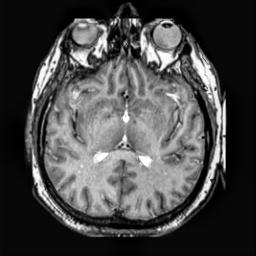

To demonstrate the effectiveness and efficiency of the proposed image fusion method , we conduct a set of comparative experiments on three image datasets. The first is composed by 8 pairs of multi-modal medical images and the second one contains 15 pairs of multi-focus gray or color natural images. These two datasets are often used in many related papers and some examples are shown in Figure 3(a) and Figure 3(b). The third one is a new multi-focus cervical cell image dataset collected by ourselves, which consists of 15 groups of color images and each group contains a series of multi-focus cervix cell images with size of or , etc. Some source examples are shown in Figure 3(c). Our source code implemented in C++ along with the new multi-focus cervical cell image dataset is available online.

We first evaluate the performance of the proposed method under varying total number of octaves and number of layers sampled per octave. The fused images of a pair of multi-modal medical images with different and are shown in Figure 4. In this example, on the one hand, when only 1 or 2 octaves are involved in constructing the DoG pyramid, the fused images fail to keep the integrity information of large size objects (e.g. eyeballs), while by increasing the value of , the integrity information of eyeballs is preserved. On the other hand, although not as significant as the increase of octave numbers , the fused image can contain more details by the increase of layer numbers . The corresponding objective quality metrics are shown in Figure 5. As shown in Figure 5(a), most of the metric values are improved as the number of octaves increases with the fixed layer numbers 3 in the global tendency and each of them tends to be stable when the number of octaves is 5. To get a relatively good quality from Figure 5(b), we can notice that some of the metric values can get a good performance when the number of layers is 3, such as the MI, SSIM, QI and VIF, though there are only a little change of all the metric values by increasing the number of layers with the fixed octave numbers 5. Because it will result in more computation burden with the increase of the value and , and for different kinds of source images, there are different performance with the diverse parameter settings. To get a trade-off between them in our experiments, we set for the multi-modal dataset, for the natural datasets and for the multi-focus cell dataset, respectively.

Figure 6 shows the fused images obtained by different methods with the multi-modal source images shown in Figure 3(a). As shown in these figures, the proposed method can produce images which preserve the complementary information of different source images well. Moreover, due to the scale-invariant structure saliency selection, our method can keep the integrity information of large size objects and the visual details simultaneously. Although the fused image generated by other methods can also capture the details to some extent, all of them fail to keep the integrity information of large size objects such as the eyeballs. Furthermore, from Figure 6(k)-6(t), the DTCWT, GFF, IM and NSCT methods may decrease the brightness and contrast while the proposed method can preserve these features and details without producing visible artifacts and brightness distortions.